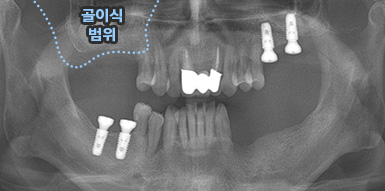

치조골이식술

골이식 임플란트

치조골 이식술이란?

치주염 등으로 치조골(잇몸뼈)의 양이 부족한 경우

치조골 이식술을 통하여 충분한 뼈의 양을 확보한 후

임플란트를 식립합니다.

뼈의 밀도가 치밀하고 단단하며, 양이 충분할수록 임플란트의 성공률이 높아집니다.

청담네오플란트는 풍부한 경험의 의료진이 치조골 이식술을 통해 치조골을 적절한 양과

밀도로 재생시킨 후 임플란트를 식립합니다. 뼈의 흡수가 심하지 않아 적은 양의

치조골 이식을 하는 경우 임플란트 식립을 동시에 진행할 수 있지만, 뼈의 흡수가

심하여 많은 양의 치조골 이식이 필요한 경우 치조골 이식술을 먼저 진행한 후,

치조골이 재생되면 임플란트를 식립하여 보다 정밀하고 안전한 시술 결과를 얻을 수 있습니다.

치조골 이식술 전후사진

B

A